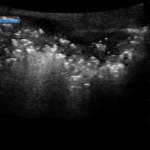

Point of care ultrasound (POCUS) utilizing a high-frequency linear probe revealed heterogeneous debris with subcutaneous air within the scrotal wall extending into the perineum consistent with necrotizing fasciitis of the perineum or Fournier’s gangrene (FG). The video shows multiple foci of gas that appear as echogenic dots with “dirty shadows” posteriorly from reverberation artifact arising from gas within the soft tissue.

Diagnosis of Fournier’s can be difficult due to the limitations of the physical exam and the wide variability of presentation of the disease. Currently, the gold standard for detecting necrotizing soft tissue infections is tissue biopsy.5 However, due to the rapidly progressive nature of FG, POCUS is a favorable initial test in making the diagnosis. POCUS has a sensitivity of 88.2%, a specificity of 93.3%, a positive predictive value of 83.3% and a negative predictive value of 95.4% in diagnosis necrotizing fasciitis.6 Key findings of FG on POCUS include a thickened scrotal wall with echogenic foci of gas with “dirty shadows.” The testes and epididymis are spared due to their separate blood supply.7 POCUS can provide an accurate and more time efficient means of making the diagnosis compared to waiting for computed tomography when confronted with a potential case of FG.